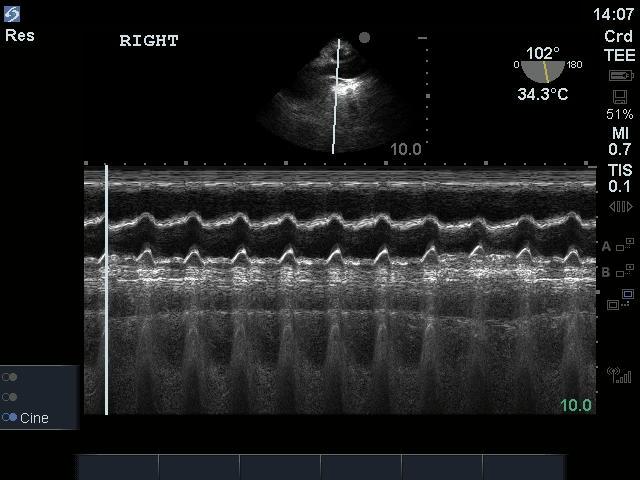

TEE Resus Volume Responsiveness Image